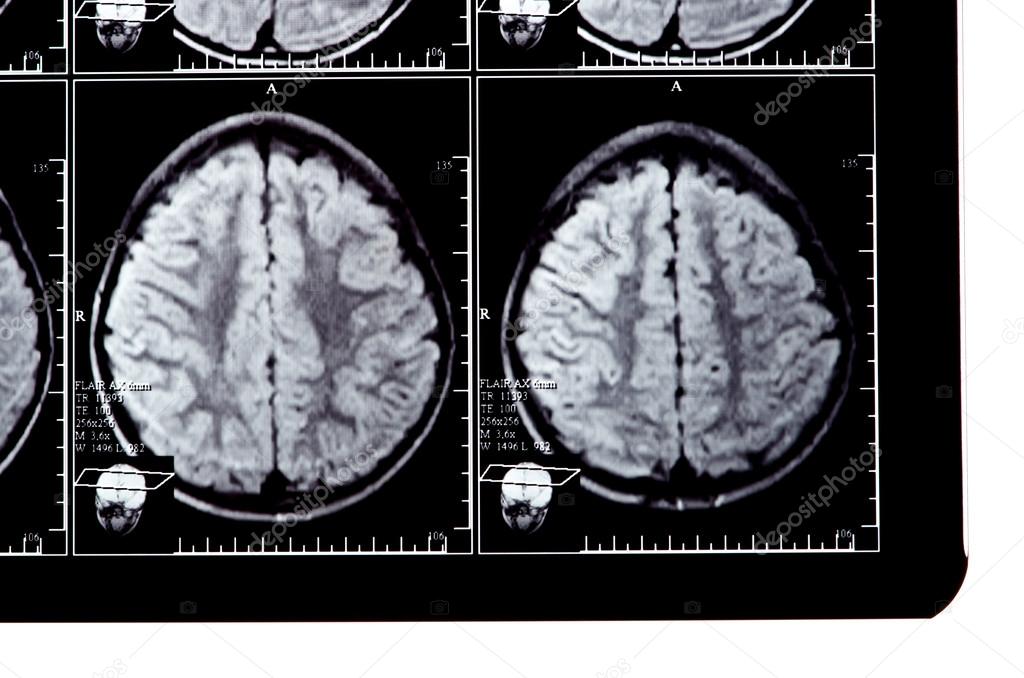

Πότε η χρήση του κινητού γίνεται προβληματική;

Τι συμβαίνει στη νέα γενιά λόγω διαδικτύου;